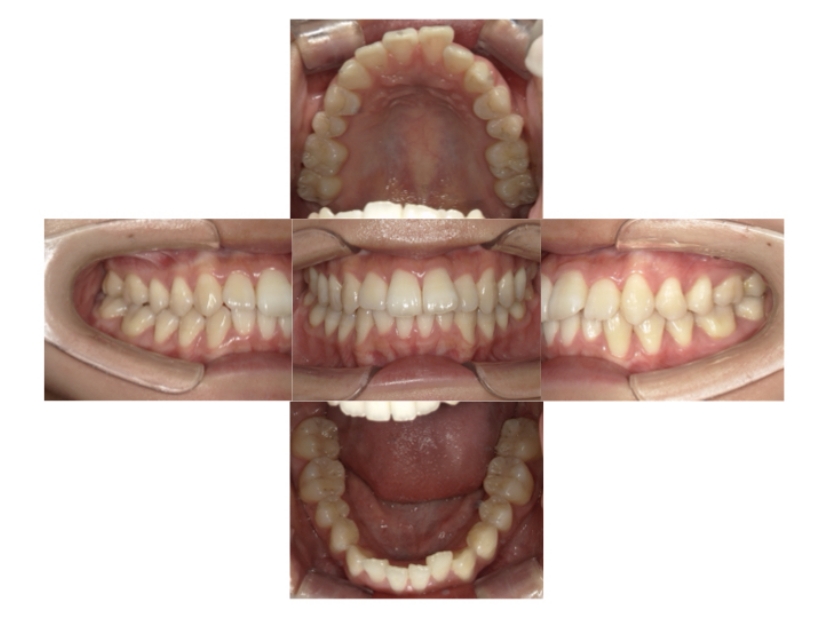

症例4

下顎前突、叢生

抜歯

ブラケット矯正

上下顎叢生、反対咬合(上下の前歯のガタガタ、若干受け口)のケースです。

装置はラビアル(上下表側)で、上下顎の小臼歯を4本抜歯を行っています。抜歯したスペースを使って、上下の叢生改善と前歯の受け口の改善を行っています。

主訴 前歯のガタガタを治したい。

年齢・性別 45歳 女性

お住まいの地域 神奈川県川崎市

治療方針 抜歯スペースを利用して上前歯の叢生(ガタガタ)の改善と受け口の改善

抜歯部位 上顎左右第一小臼歯、下顎左右第二小臼歯

使用装置 ラビアル(上下表側)、顎間ゴム

治療期間 2年6か月

治療回数 20回

リテーナー クリアリテーナー

BEFORE

AFTER